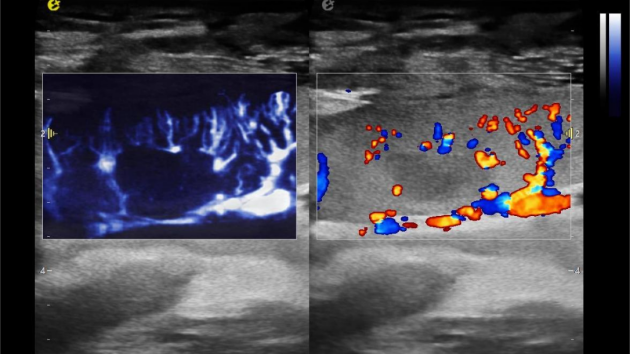

1) 实时查看血管吻合情况,确保新肾"通电"后动、静脉血流是否畅通;

2) 监测肾门处血流频谱及时干预血栓的形成,减少术后血管并发症的发生率;

3) 观察肾皮质的血流灌注情况,评估肾移植的成功率。

超微视血流显像评估肾移植术后灌注情况

这一项无创、无辐射操作简便且无需造影剂的黑科技,相当于用"高速摄像机"记录血液细胞的运动轨迹,让血管并发症"无处遁形。

从术前评估到术中到术后,再到终身监护,当20-50μm级的超微血流信号在屏幕上跳动,我们看到的不仅是技术的精进,更是生命的律动。iPlane Vascular正在重新定义肾移植监护的标准——让医生拥有了"显微视力",让每一个微小血管的异常都无所遁形,让每一次免疫排斥的萌芽都被及时扼制。